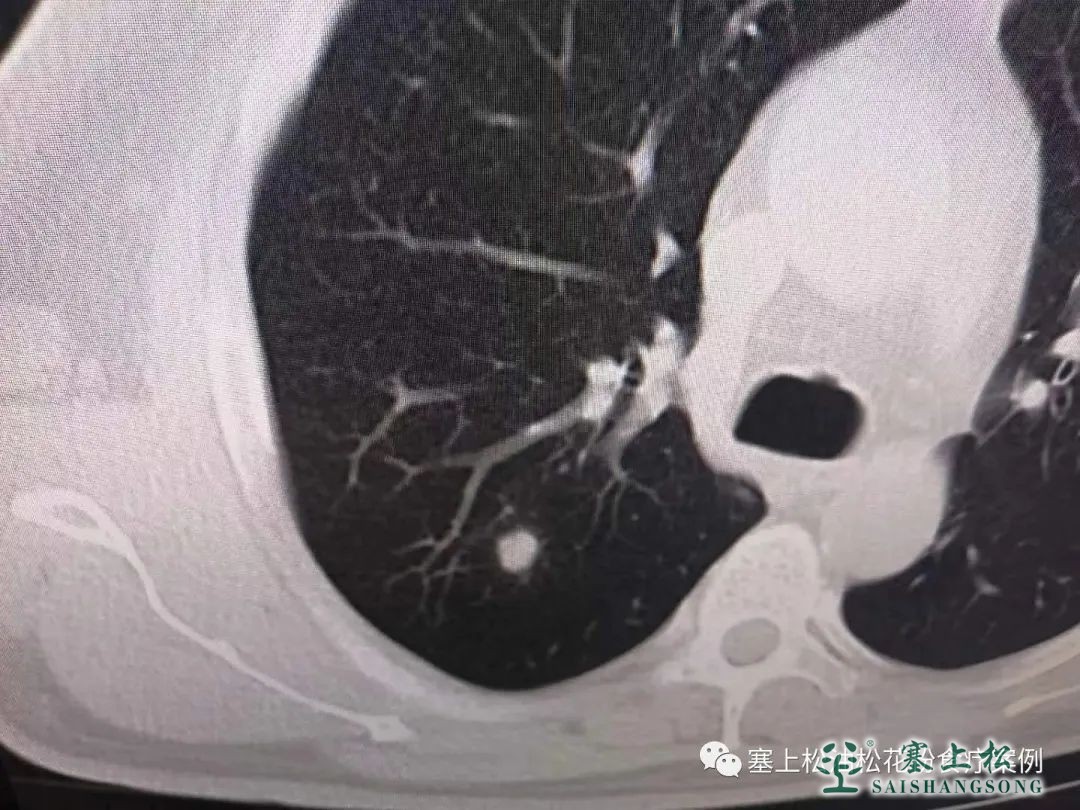

后来2017年和18年的时候,因为单位组织体检,在中心医院做肺部CT扫描的时候,就发现我有肺结节,0.2cm~0.5cm大小。在小于0.8cm的情况下几乎不需要什么处理,只是要求你然后做好监测,一旦长得太大了,超过1cm了,或者长时间有症状。就需要手术切除。

看到问题以后,曾经也一度非常紧张,也是四处求医,因为本身在医院也有一些同学朋友,所以就让他们给我拿主意,2019年的时候,呃,这个结节大的已经超过一部分了,到2021年的时候。就已经远远1cm了,可以说是完全达到了手术指标。当时就想去山东或北京做射频消融术,把这个节点烧掉。

第一次崔总就给我拿了十几袋,大剂量服用。2022年我在做CT的时候,就发现它就非常小了,2022年8-9月份吧,我到CT室再次筛查的时候,主任就很惊讶的告诉我:你这个结节已经没有了,完全没有了。